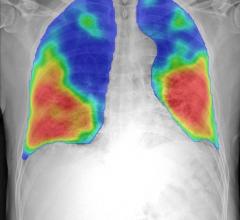

July 10, 2020 — Infervision announced U.S. Food and Drug Administration (FDA) 510(K) clearance of the InferRead Lung CT ...

July 9, 2020 — With increased lung CT exam paradigms being used in the current COVID-19 (SARS-CoV-2) outbreak, and an ...

June 15, 2020 — A mobile platform for lung cancer screening with low-dose computed tomography (CT) can be developed with ...